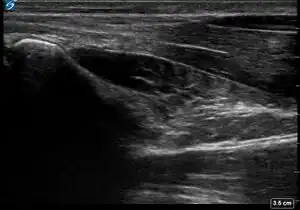

| 4 | Probe is set to the proper depth of 4 cm when evaluating the pronator quadratus muscle. | ![]() |

![]() |

| 5 | All features are properly labelled. | ![]() |